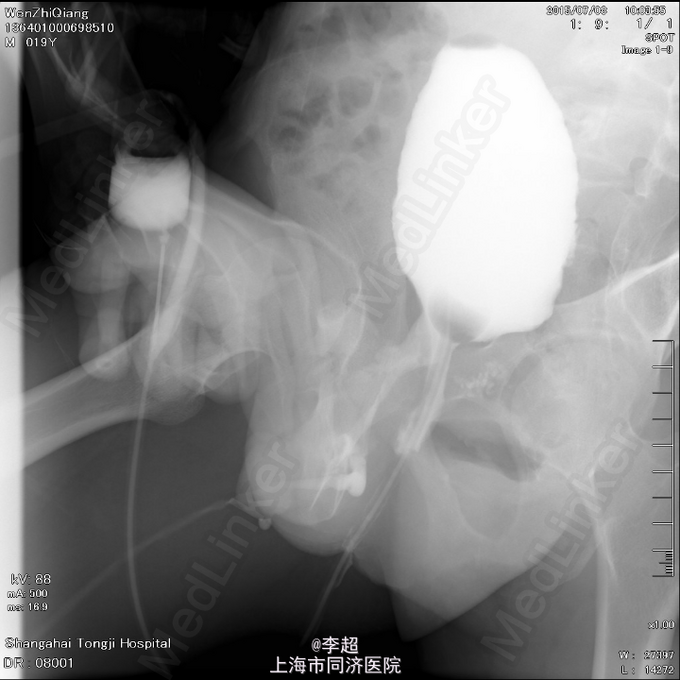

择期行耻骨下缘切除+阴囊皮瓣代尿道成形+尿道膀胱拖入术 手术过程:行会阴部倒Y形切口切口,切口包括会阴部尿道造口处,术中见阴茎部尿道存在尿道-阴茎皮肤瘘道,予切除瘘道。分离后尿道,探查见后尿道疤痕明显,并且于耻骨相连,局部粘连严重。考虑有假道存在可能,遂做耻骨上纵行切口4cm,探查膀胱发现距目前尿道口处1cm处前方存在另一内口,为盲道,盲端被变形耻骨完全遮挡。遂使用骨刀劈凿穿耻骨并切除耻骨下缘,凿通至膀胱盲道,将盲端断断显露,使用膀胱镜探查盲道,见盲端口膀胱肌肉括约功能较好,推断为真性尿道,使用左侧阴囊及大腿根部皮瓣约8cm*3cm大小,分离皮瓣下组织血管形成血管蒂,翻转皮瓣形成尿道,将皮瓣尿道近端拖入膀胱,与真性尿道膀胱黏膜处直针缝合。另将皮瓣尿道远端与阴茎部正常尿道粘膜缝合,留置F14号导尿管,假道处尿道予留置Foley14导尿管。

随访 讨论

术后6周拔除尿管,患者排尿通畅,无尿失禁,尿流率17ml/s, 术后8周拔除假道内导尿管,拔管后2周假道自行闭合。 该患者尿道缺失长,且尿道断裂处被变形耻骨完全遮挡,故外院手术时,从骨头下方吻合,形成假道。 本次手术后,恢复正常的尿道结构,和尿道内口位置,故尿失禁症状消失。 但手术难度极大,缝合时没有操作空间,凿去骨头后,仍仅能行直针拖入缝合。但吻合较确切,故术后效果良好。